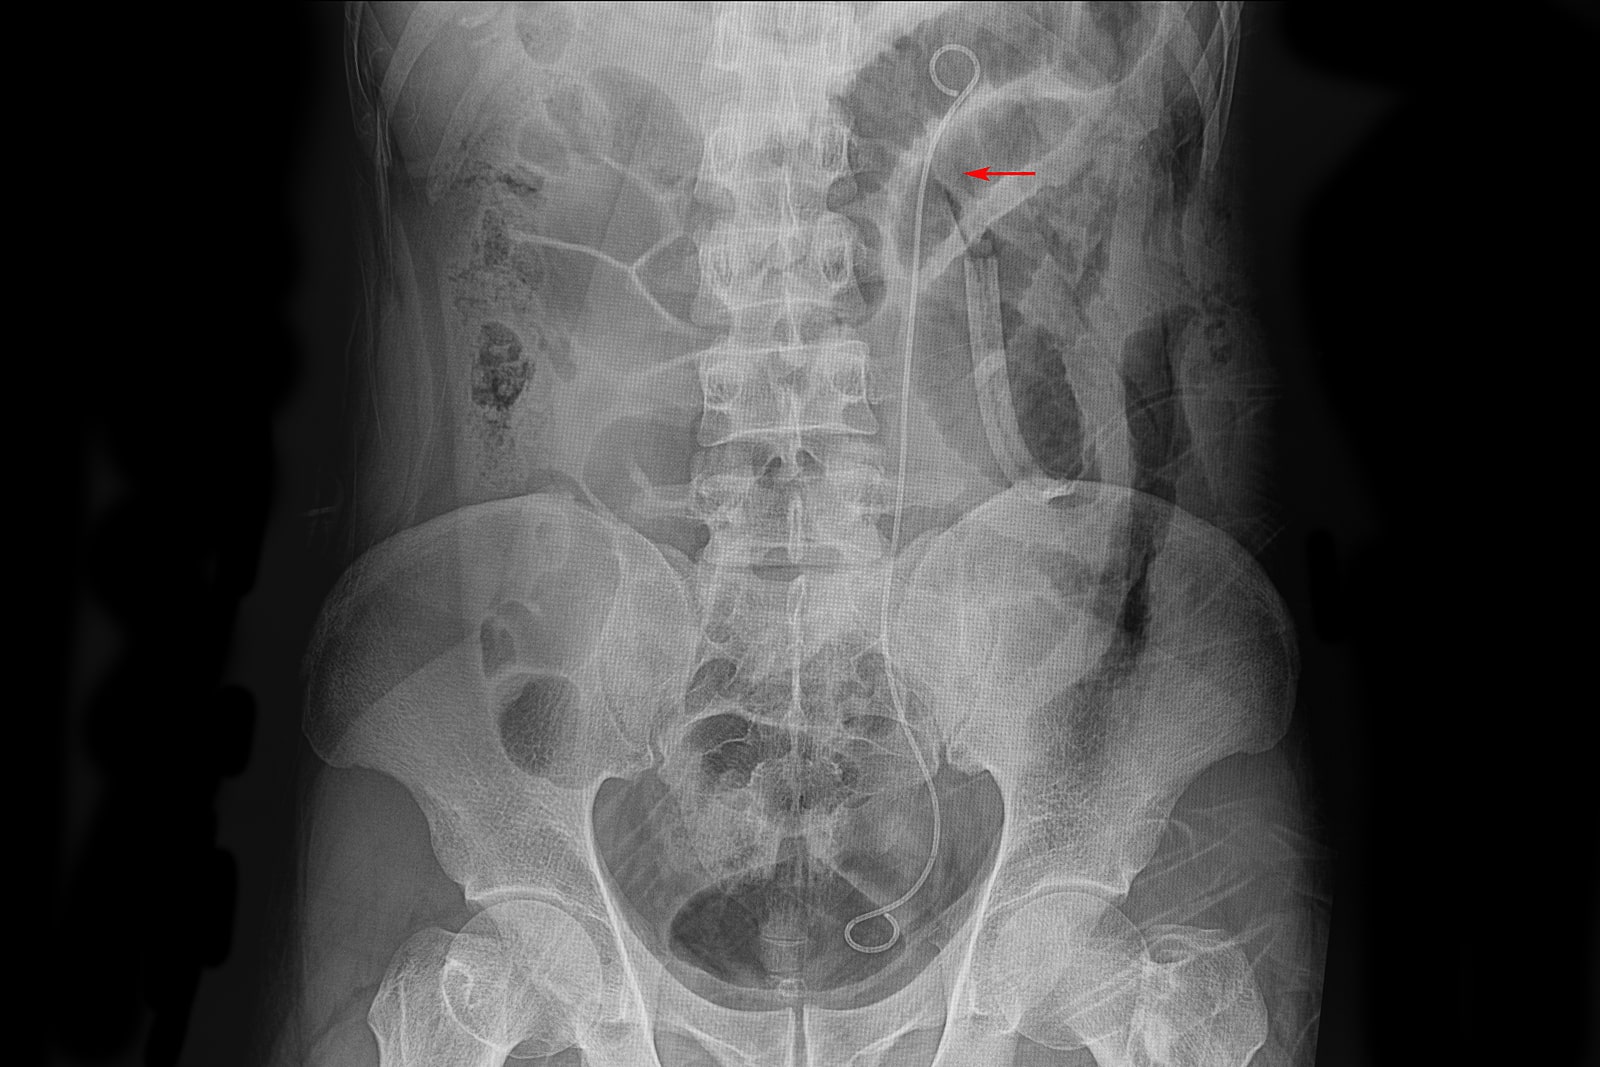

Ureteric Stent Going home Milton Keynes University Hospital new arrivals, Ureteral Stent Placement Memorial Sloan Kettering Cancer Center new arrivals, Ureteric Stent Patient Information Brochures Mater Group new arrivals, Ureteric stenting CIRSE new arrivals, Ureteroscopy and ureteric stenting for ureteric stones Urology new arrivals, Ureteric stent Macmillan Cancer Support new arrivals, IJMS Free Full Text Functional Properties of Polyurethane new arrivals, Ureteric Stent Insertion VIRQ new arrivals, Ureteric stent insertion Chelsea and Westminster Hospital NHS new arrivals, Consent Retrograde Ureteric Stent Insertion TeachMeSurgery new arrivals, Having a Ureteral Stent Saint Luke s Health System new arrivals, Ureteral Stents new arrivals, Dr Tim Nathan Urology Insertion and Removal of Ureteric Stents new arrivals, Ureteral stents are flexible tube like devices with holes new arrivals, Ureteral Stent for Parents Nemours KidsHealth new arrivals, Ureteral Stent Placement What is a ureteral stent Urology Austin new arrivals, Ureteral Stents What you need to know new arrivals, What Is Ureteral Stenting Procedure and Recovery new arrivals, Use of cystourethroscopy to remove an indwelling double J ureteral new arrivals, Ureteral Stent My Kidney Stone Boston Scientific new arrivals, Enhance Comfort and Recovery with Ureteric Stents new arrivals, Ureteral Stent Keystone Urology Specialists new arrivals, Abdominal X ray Artifacts Renal and ureteric stents new arrivals, What to Expect from a Ureteral Stent Advanced Urology new arrivals, Ureteric Stents new arrivals, Your Guide to Ureteral Stents For Kidney Stones Worst Pain Ever new arrivals, Cystoscopy and Ureteral Stent Placement new arrivals, Determination of urinary prostaglandin E2 as a potential biomarker new arrivals, Nephrostomy and ureteric stenting CIRSE new arrivals, Outcomes of outpatient ureteral stenting without fluoroscopy at new arrivals, Ureteral Stents Boston Scientific new arrivals, Ureteral Stent Placement new arrivals, Surface engineered biomaterials and ureteral stents inhibiting new arrivals, Ureteric Stent Insertion OneWelbeck Men s Health new arrivals, Calcified ureteric stent Radiology Case Radiopaedia new arrivals.